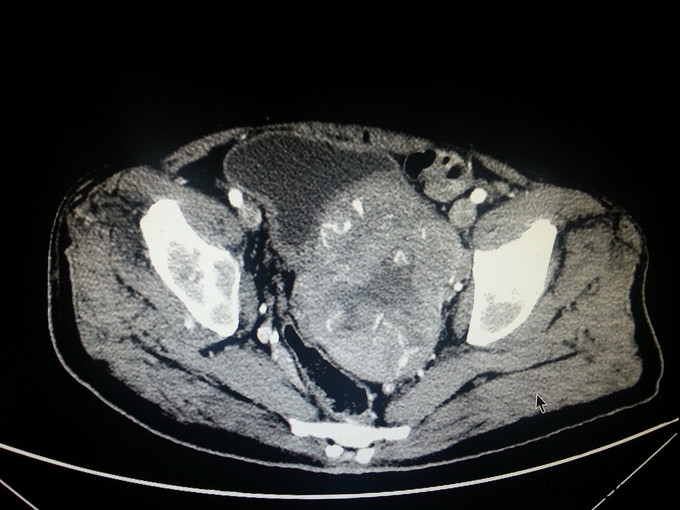

患者,男,68岁,因门诊CT检查发现前列腺肿瘤、骨转移入院

前列腺穿刺病理 :前列腺癌 Gleason4+4 PSA>100ng/ml fPSA>30ng/ml

患者入院后经会阴前列腺穿刺活检,病理诊断为前列腺癌 Gleason4+4 ;予以口服氟他胺以及静脉注射唑来膦酸、戈舍瑞林缓释剂皮下注射治疗; 治疗半年后复查 CT提示前列腺肿瘤缩小;PSA45ng/ml;患者一般情况明显好转